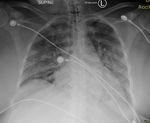

failure. Her condition worsened over a period of one week. Chest X-Ray, at the time of arrival, showed

bilateral patchy opacities consistent with COVID-19 pneumonia. After an extensive review of her labs and

FIGURE 1: Bilateral patchy opacities consistent with COVID-19

pneumonia